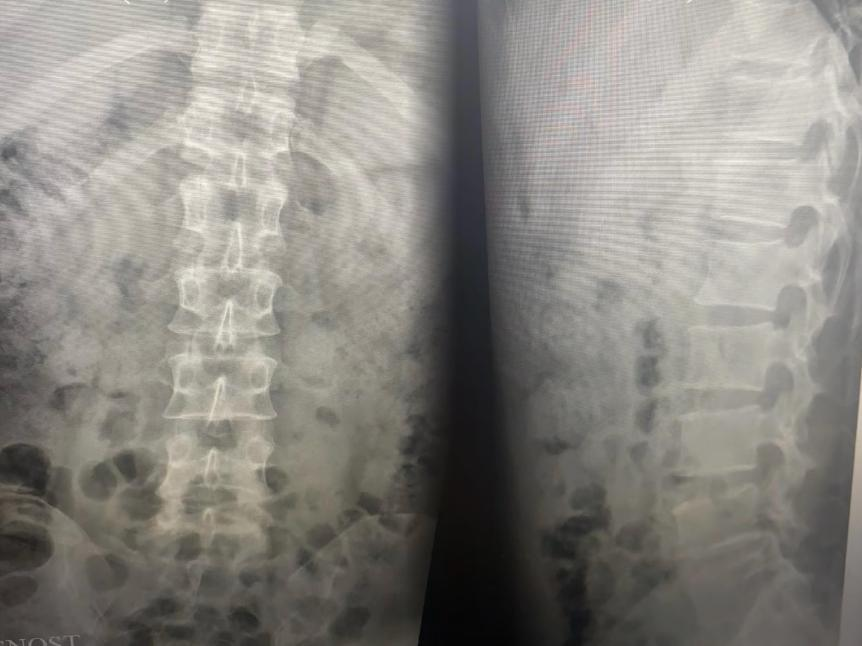

▲术后复查x线情况